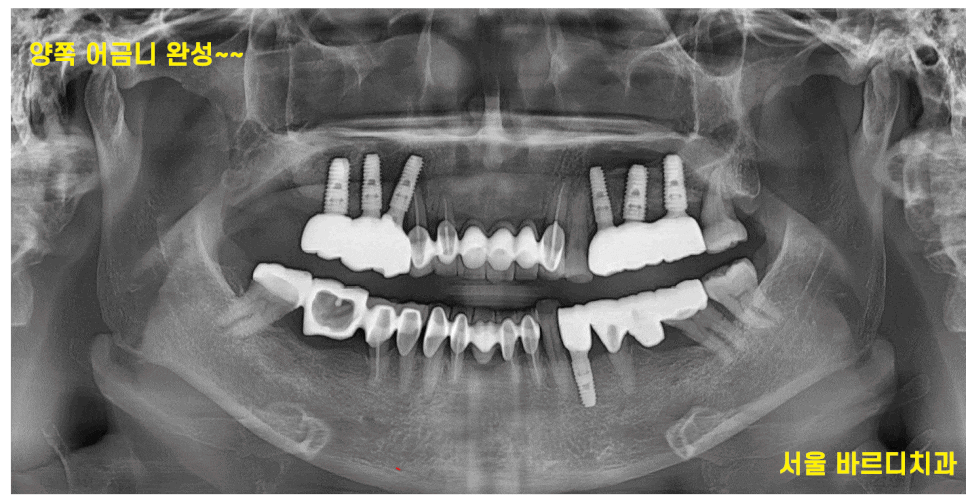

240809

임플란트 완성 사진입니다.